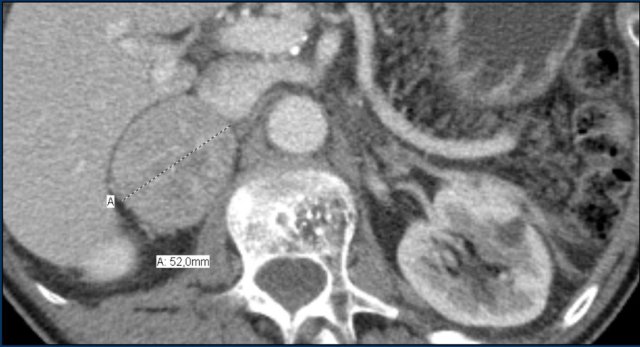

These images are of a 65- year-old female patient with an incidental discovery of a right adrenal mass on an abdominal ultrasound performed for renal stones.

The presence of microscopic fat is demonstrated by the signal drop on the opposed-phase image.

The patient was followed for 2 years, because the lesion is slightly inhomogeneous and measures 5.2 cm.

The lesion did not change in size and was not hormonally active.

It was diagnosed as a lipid-poor adenoma.